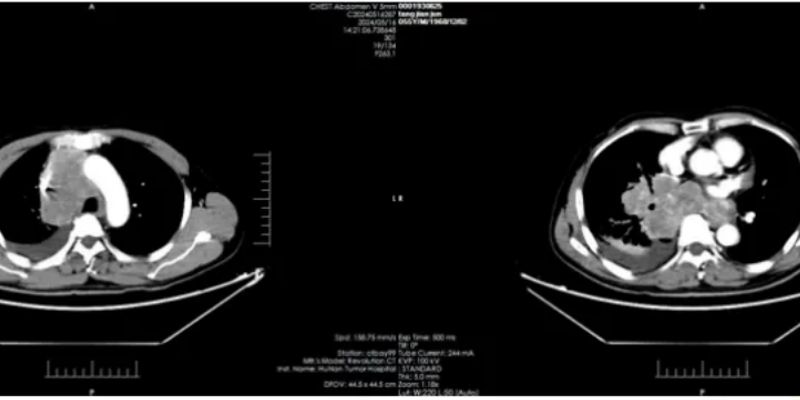

近日,3期NETTER-2临床试验数据显示,对于新确诊的2-3级、生长抑素受体阳性(SSTR)的晚期胃肠胰神经内分泌肿瘤(GEP-NETS)患者,使用新型抗癌疗法——Lutathera联合长效奥曲肽(Octreotide)一线治疗,可显著改善他们的肿瘤无进展生存期。